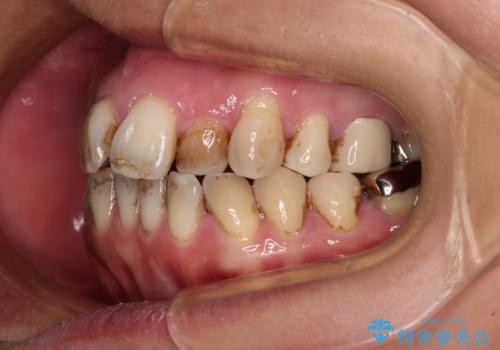

- かつて抜歯矯正を行ったものの、後戻りをしてしまったとのことで来院された患者様です。

上顎前歯が前突し、隣の歯が裏側に移動してきている状態でした。

日頃から飲まれる飲み物の影響で着色しやすいため、来院の度に着色除去のクリーニングも行っていました。